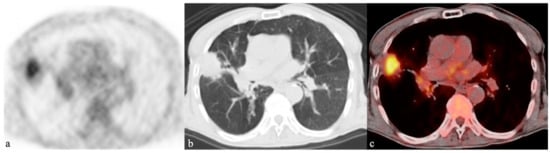

- Sathekge, M.M.; Maes, A.; Pottel, H.; Stoltz, A.; van de Wiele, C. Dual time-point FDG PET-CT for differentiating benign from malignant solitary pulmonary nodules in a TB endemic area. S. Afr. Med. J. 2010, 100, 598–601. [Google Scholar] [CrossRef] [PubMed]

- Heysell, S.K.; Thomas, T.A.; Sifri, C.D.; Rehm, P.K.; Houpt, E.R. 18-Fluorodeoxyglucose positron emission tomography for tuberculosis diagnosis and management: A case series. BMC Pulm. Med. 2013, 21, 13–14. [Google Scholar] [CrossRef]

- Chang, J.M.; Lee, H.J.; Goo, J.M.; Lee, H.Y.; Lee, J.J.; Chung, J.K.; Im, J.G. False positive and false negative FDG-PET scans in various thoracic diseases. Korean J. Radiol. 2006, 7, 57–69. [Google Scholar] [CrossRef]